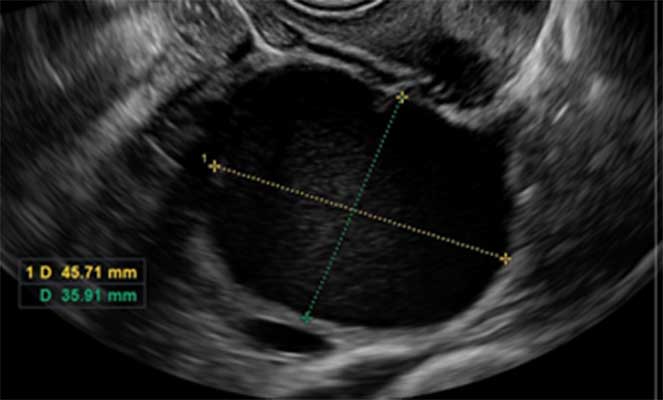

Cisto de Ovário

O que é cisto de…

Os cistos ovarianos são formações saculares preenchidas por líquido ou substância semi-sólida que se desenvolvem nos ovários das mulheres. Os cistos ovarianos afetam mulheres de…